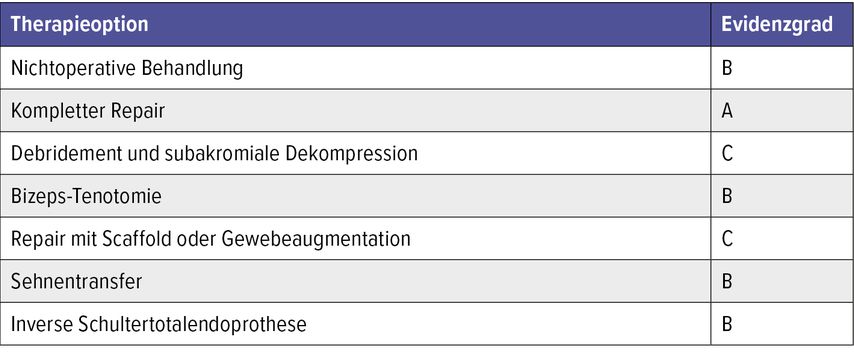

Tabelle 2 zeigt die Übersicht der essenziellen Therapieoptionen bei Rezidiven oder Rotatorenmanschetten-Sehnendefekten.

Tab. 2: Essenzielle Therapieoptionen bei Rezidiven oder Rotatorenmanschetten-Sehnendefekten, um die bestmögliche Behandlungsstrategie auf Grundlage der aktuellen wissenschaftlichen Erkenntnisse auszuwählen (basierend auf der verfügbaren Evidenz). A: Gute Evidenz aus Level-I-Studien, um eine Intervention zu empfehlen oder abzulehnen. B: Mäßige Evidenz aus Level-II- oder -III-Studien, um eine Intervention zu empfehlen oder abzulehnen. C: Schwache Evidenz aus Level-IV- oder -V-Studien, um eine Intervention zu empfehlen oder abzulehnen